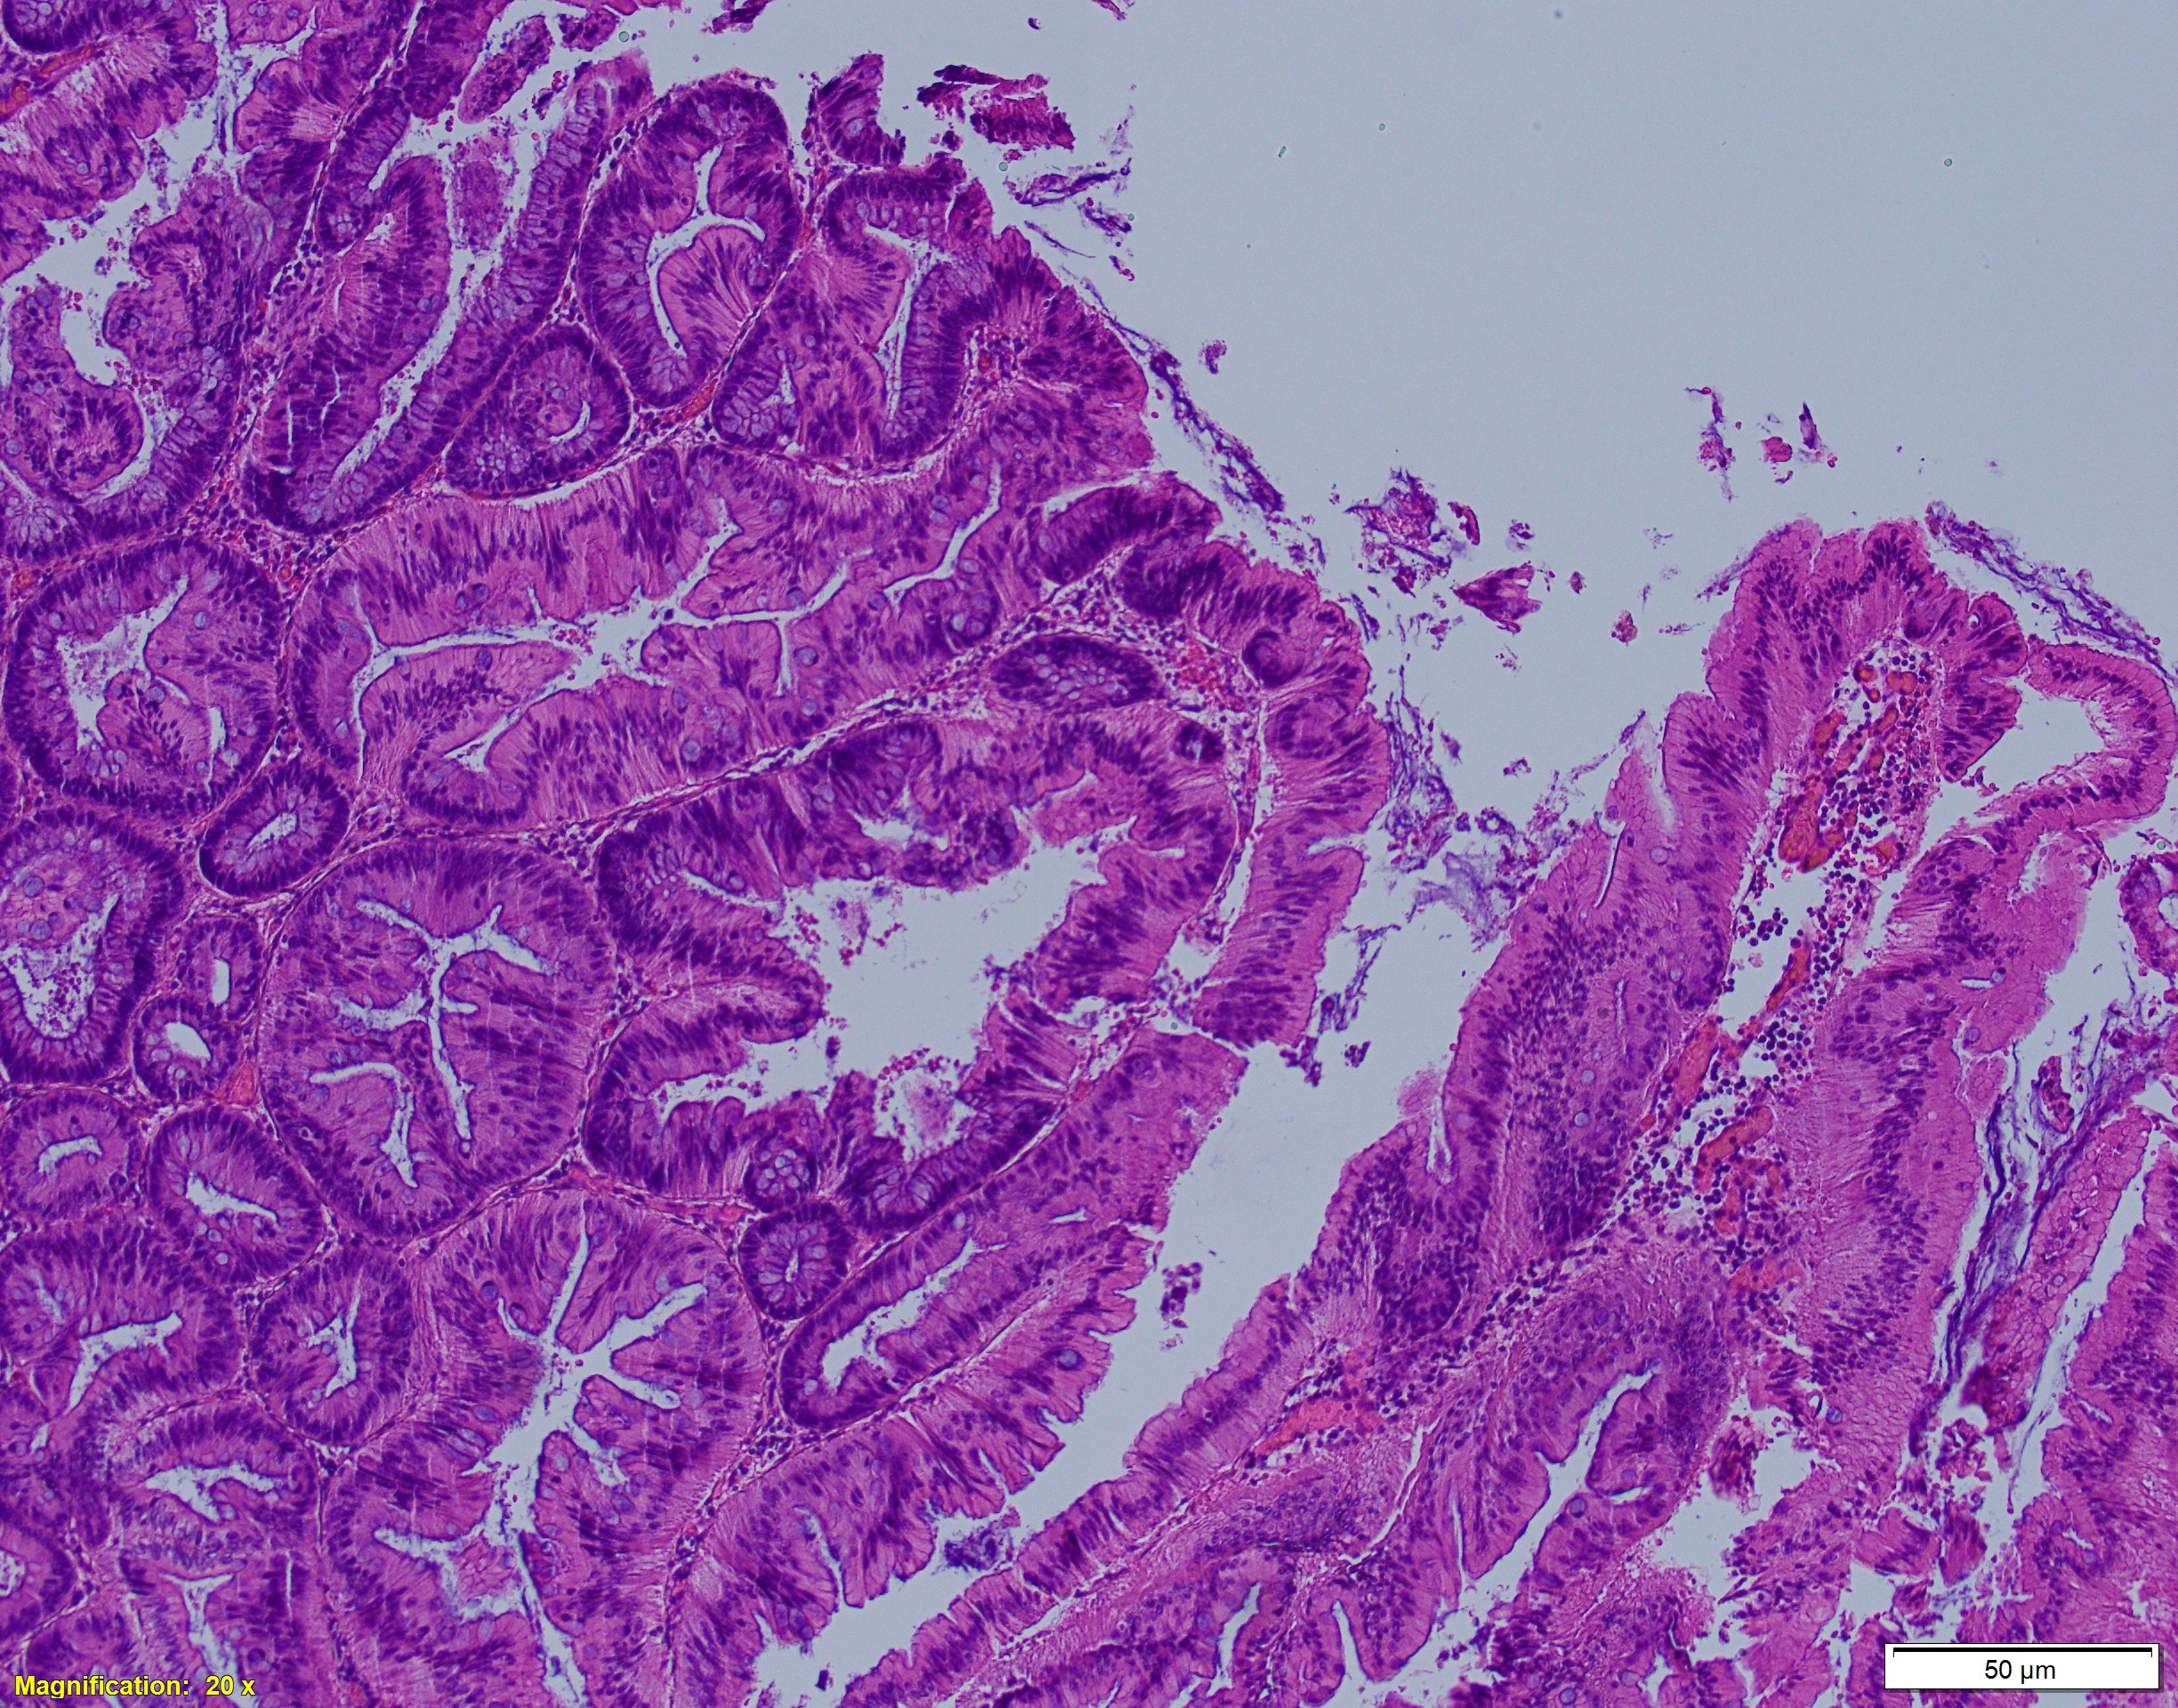

Answer: B, Traditional serrated adenoma

Traditional serrated adenoma is a serrated lesion, often associated with high grade dysplasia or invasive adenocarcinoma. It constitutes for 1-2% of colorectal adenomas and is mostly found in the left colon of elderly patient (mean age of 63 years). Endoscopically, it can present as large protuberant polyp in the distal colorectum or as flat lesion in the proximal colon; it is usually larger than 1cm in size. Morphologic findings include prominent, slit-like serration of glands within the polyp with complex architecture (infolding, budding, and papillary tufting). The lesion consists of tall/columnar neoplastic cells with hypereosinophilic cytoplasm with crowded pseudostratified ad elongated (“pencillate”) nuclei. Another characteristic feature is an ectopic crypt formation (small “budding”crypts). Cytologic dysplasia can be recognized by lack of surface maturation, immature goblet cells, and multiple upper zone mitoses. On the molecular level, traditional serrated adenoma most frequently harbor KRAS mutations, although BRAF mutations, as well as MSI, CIMP had also been reported. Differential diagnosis includes tubular/tubulovillous adenoma, which is by far the most common type of colorectal adenomas, as well as sessile serrated adenomas.